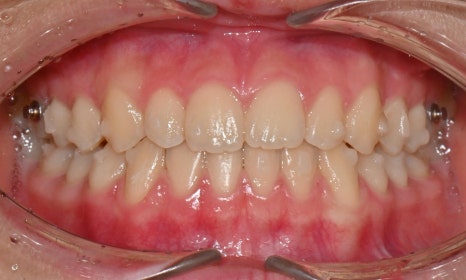

치료 시작 8개월 후 사진으로 치아 사이에 벌어졌던 공간은 거의 다 닫혔으며 어금니 교합도 개선되었습니다. 위아래 치아 중심선도 일치하고 있습니다. 현재 미세하게 치아 위치 조정하며 마무리 중입니다.

치료 시작 8개월 후

치료 전후 구내사진